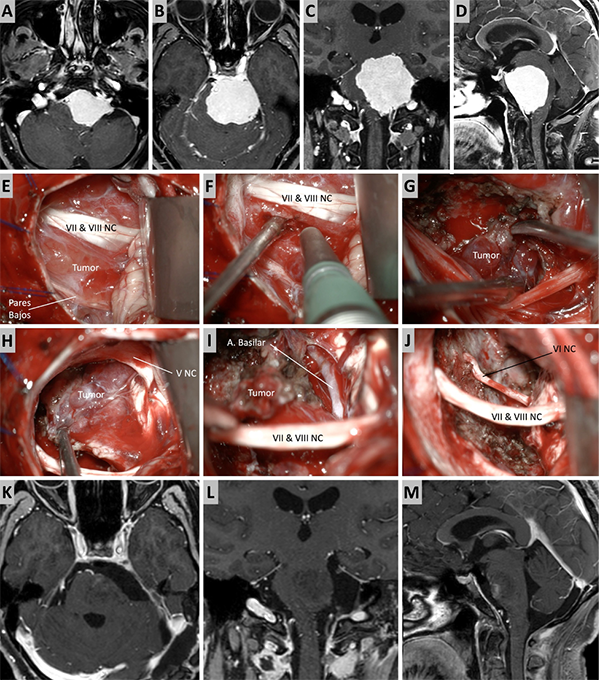

Figura 3. Caso ilustrativo #1. MRPC con implantación petroclival, extensión a la fosa media y compromiso de la incisura tentorial. Paciente con audición conservada. A. Corte axial sobre la región clival media. B. Corte axial sobre la región clival superior. Corte Coronal. D. Corte sagital donde se observa el efecto compresivo sobre el tallo cerebral. E-J. Se realizo un abordaje retrosigmoideo. K-N. Se muestra las imágenes en distintos cortes con el resultado quirúrgico. Residuo tumoral incipiente sobre la incisura tentorial.